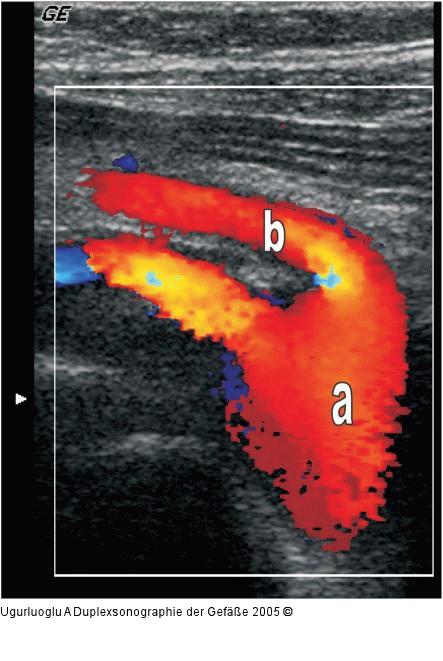

Abbildung 5: Duplexsonographie - A. mesenterica sup. a) Aorta abdominalis, b) Arteria mesenterica superior. Längsschnitt |

Abbildung 5: Duplexsonographie - A. mesenterica sup.

a) Aorta abdominalis, b) Arteria mesenterica superior. Längsschnitt |